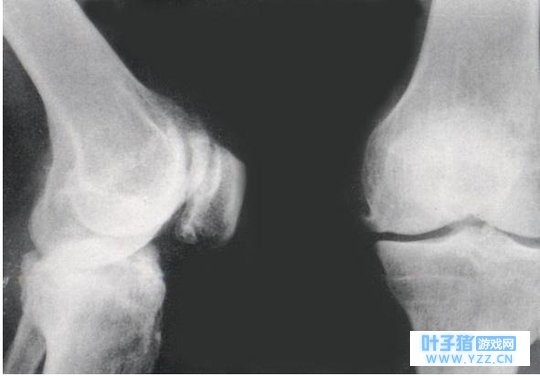

膝关节炎的不规范“俗称”:骨质增生、骨刺。膝关节炎是一种以关节软骨的变性、破坏及骨质增生为特征的慢性关节病。“骨刺”“骨质增生”,其实是老百姓对骨性关节炎的不规范的俗称。

因为骨质增生并不等于骨关节炎,医学上并没有骨质增生这种病。它只是关节退变的影像学表现,有骨质增生并不表明有膝关节炎的存在,因为有些骨质增生并没有伴随什么症状。“膝关节炎患者通常有骨质增生存在”,这是对的,但反之推断“骨质增生就是膝关节炎”,则不能成立。